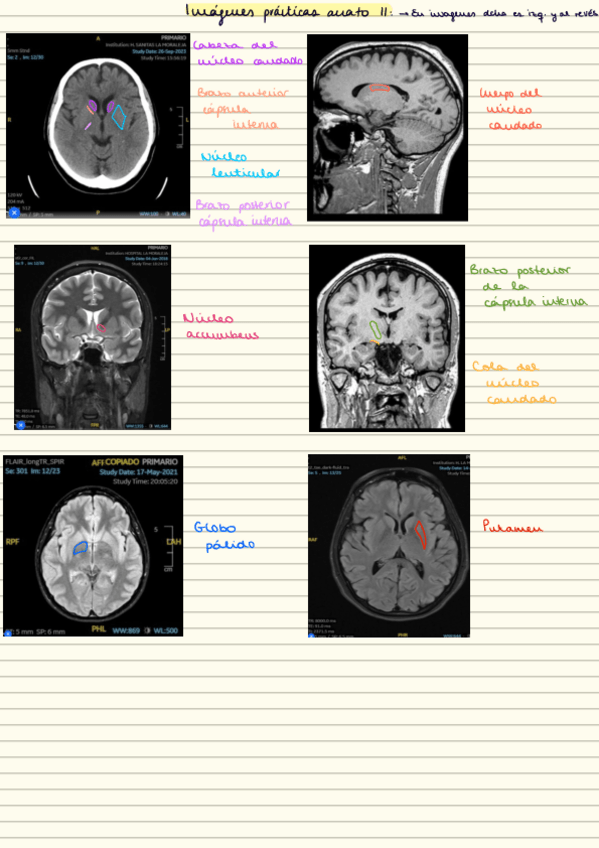

He publicado nuevos apuntes de 2º Anatomía Humana II: practicas-neuroanatomia.pdf

He publicado nuevos apuntes de 2º Anatomía Humana II: practicas-imagenes-resonancias.pdf

Este es uno de los dos modelos de examen que se hizo en la convocatoria adelantada de las prácticas de neuro (la imagen de los ganglios basales no era un TAC pero no he encontrado la foto que pusieron)